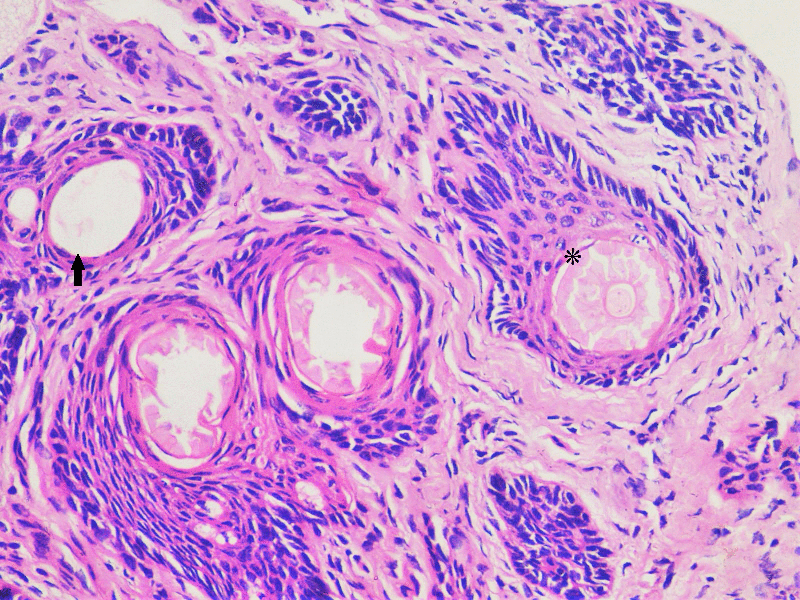

After discussing the surgery with her parents, an informed consent was obtained and an excisional biopsy was performed in the operating room under complete aseptic conditions. The left upper eyelid was injected locally with a 1:1 mixture of Xylocaine (2%) and Epinephrine (1:100,000). The tissue specimen was removed as a circular mass with a diameter of 8 mm that included skin, subcutaneous tissue with a centrally situated hair tuft, and some normal lashes located on one side of the abnormal hair tuft (Figure 2 [Fig. 2]). The specimen was sent for histopathology and the report described both sebaceous glands (SG) and epithelial lined apocrine Molls glands (MG) adjacent to subcutaneous pilosebaceous follicle (PSF) (Figure 3 [Fig. 3] and Figure 4 [Fig. 4]). No other glands could be identified. The patient was examined at 1 week, 4 weeks and 3 months postoperatively and no evidence of local recurrence was found.